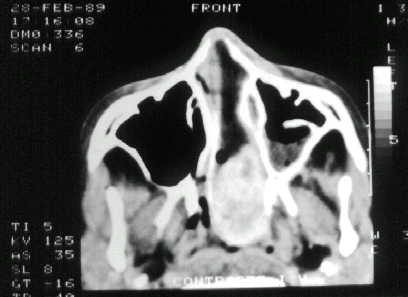

D7. DIAGNOSTICO POR

IMAGEN

¨La

interpretación exige un buen conocimiento anatómico.¨ Determina

el diagnóstico, extensión y precisa el acto quirúrgico

¨TAC

-

TRIDIMENSIONAL

¨RMN

¨ARTERIOGRAFIA

CON EMBOLIZACIÓN

¨SCANER

HELICOIDAL